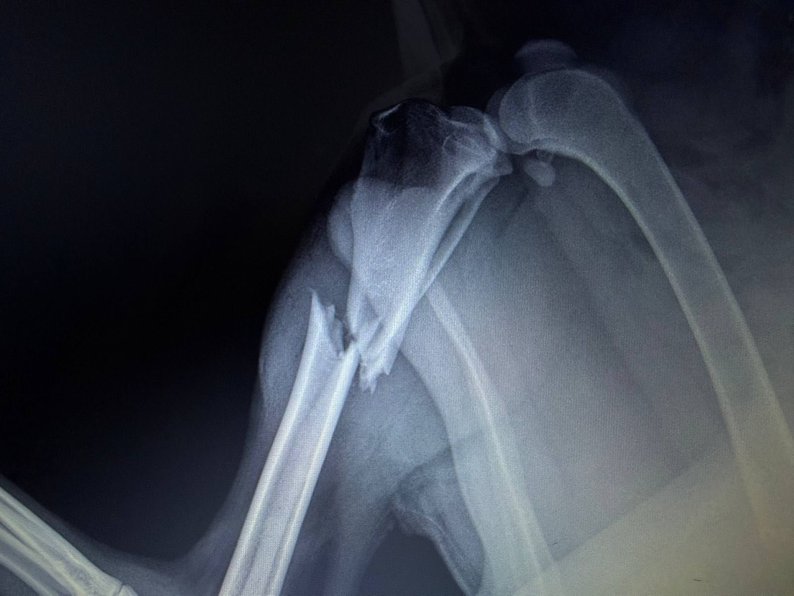

Водій збив собаку в районі м'ясокомбінату та лишив його на проїжджій частині. До клініки тварину привезла інша водійка. У собаки діагностували перелом гомілки задньої лапи.

Перелам гомілки у собаки. Центр поводження з тваринами/FacebookПесика одразу оглянули та провели повне обстеження. Малюк зовсім молодий, йому ще немає й двох років. Попри сильний біль і пережитий стрес, він виявився дуже контактним, грайливим і постійно тягнувся до людей. Наші лікарі ухвалили рішення про термінову операцію. Втручання пройшло успішно. Лапка заживає, песик поступово відновлюється та з кожним днем почувається краще.